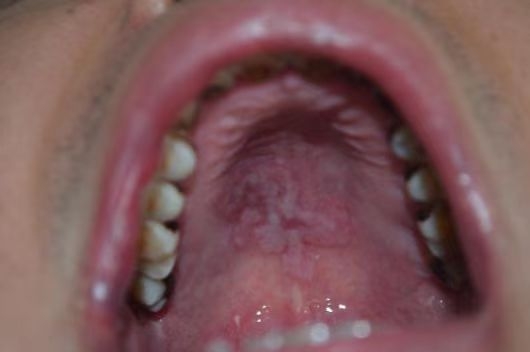

梅毒患者口腔

HIV患者毛状白斑伴真菌感染